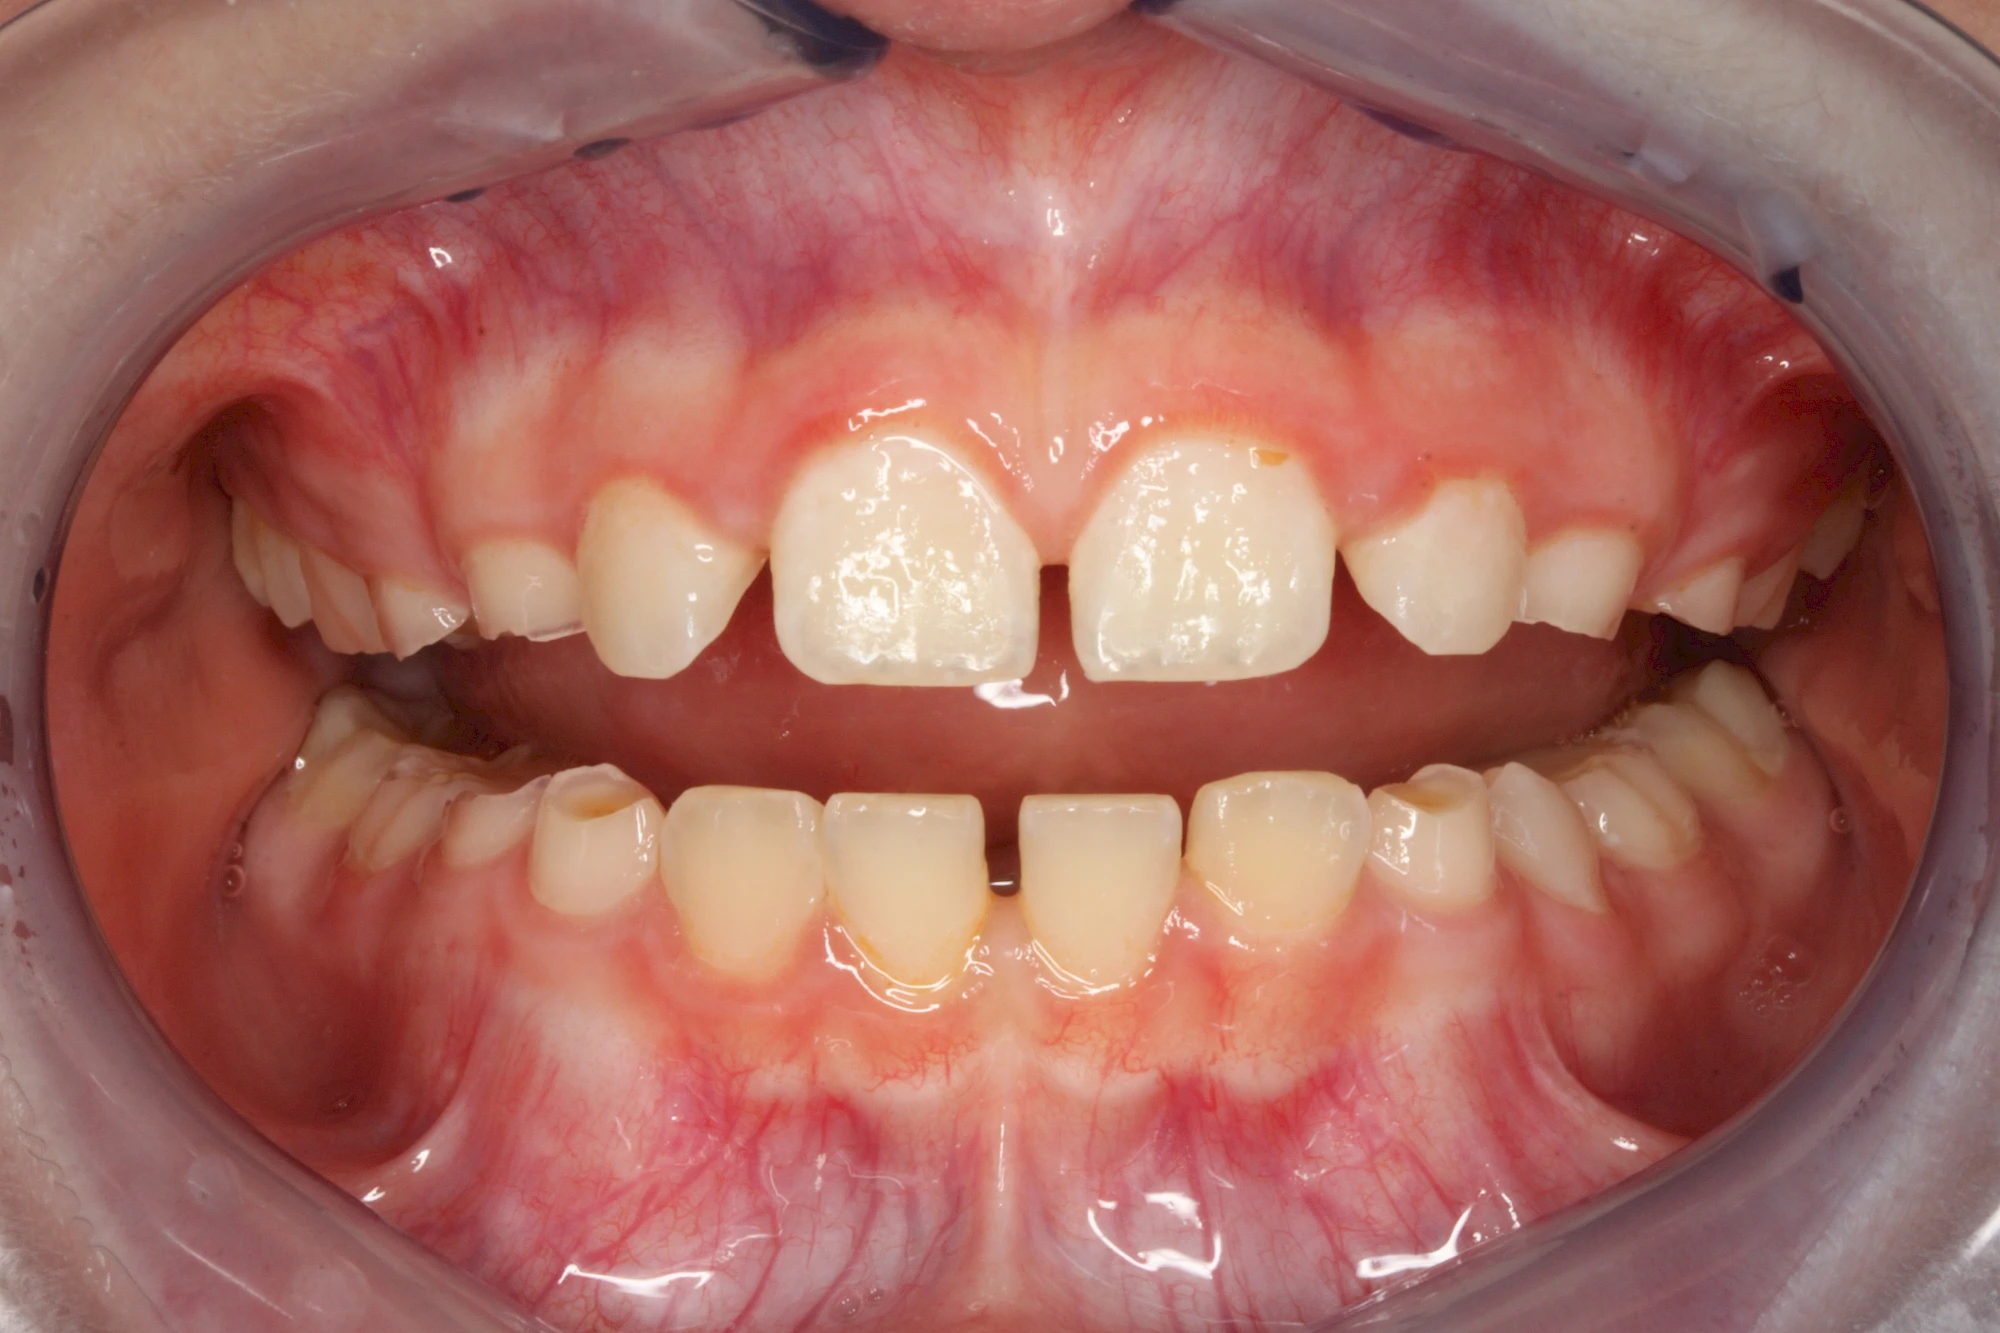

Über die Zeit können verschiedene Prozesse die Zahnhartsubstanzen aufzehren:

- Abnutzung durch Kauen (Abrasion) oder duch durch übermäßiges Knirschen bzw. Pressen (Attrition)

- Säurebedingte Auswaschung (Erosion)

- Knirschen bzw. Pressen und ungünstige Putztechnik (Druck): keilförmige Defekte

Die Zähne können dabei auf Reize (warm, kalt, süß, sauer) oder auch beim Zähneputzen empfindlich oder schmerzhaft sein. In allen diesen Fällen ist es sinnvoll, den Zahnarzt zu kontaktieren und das weitere Vorgehen abzustimmen.